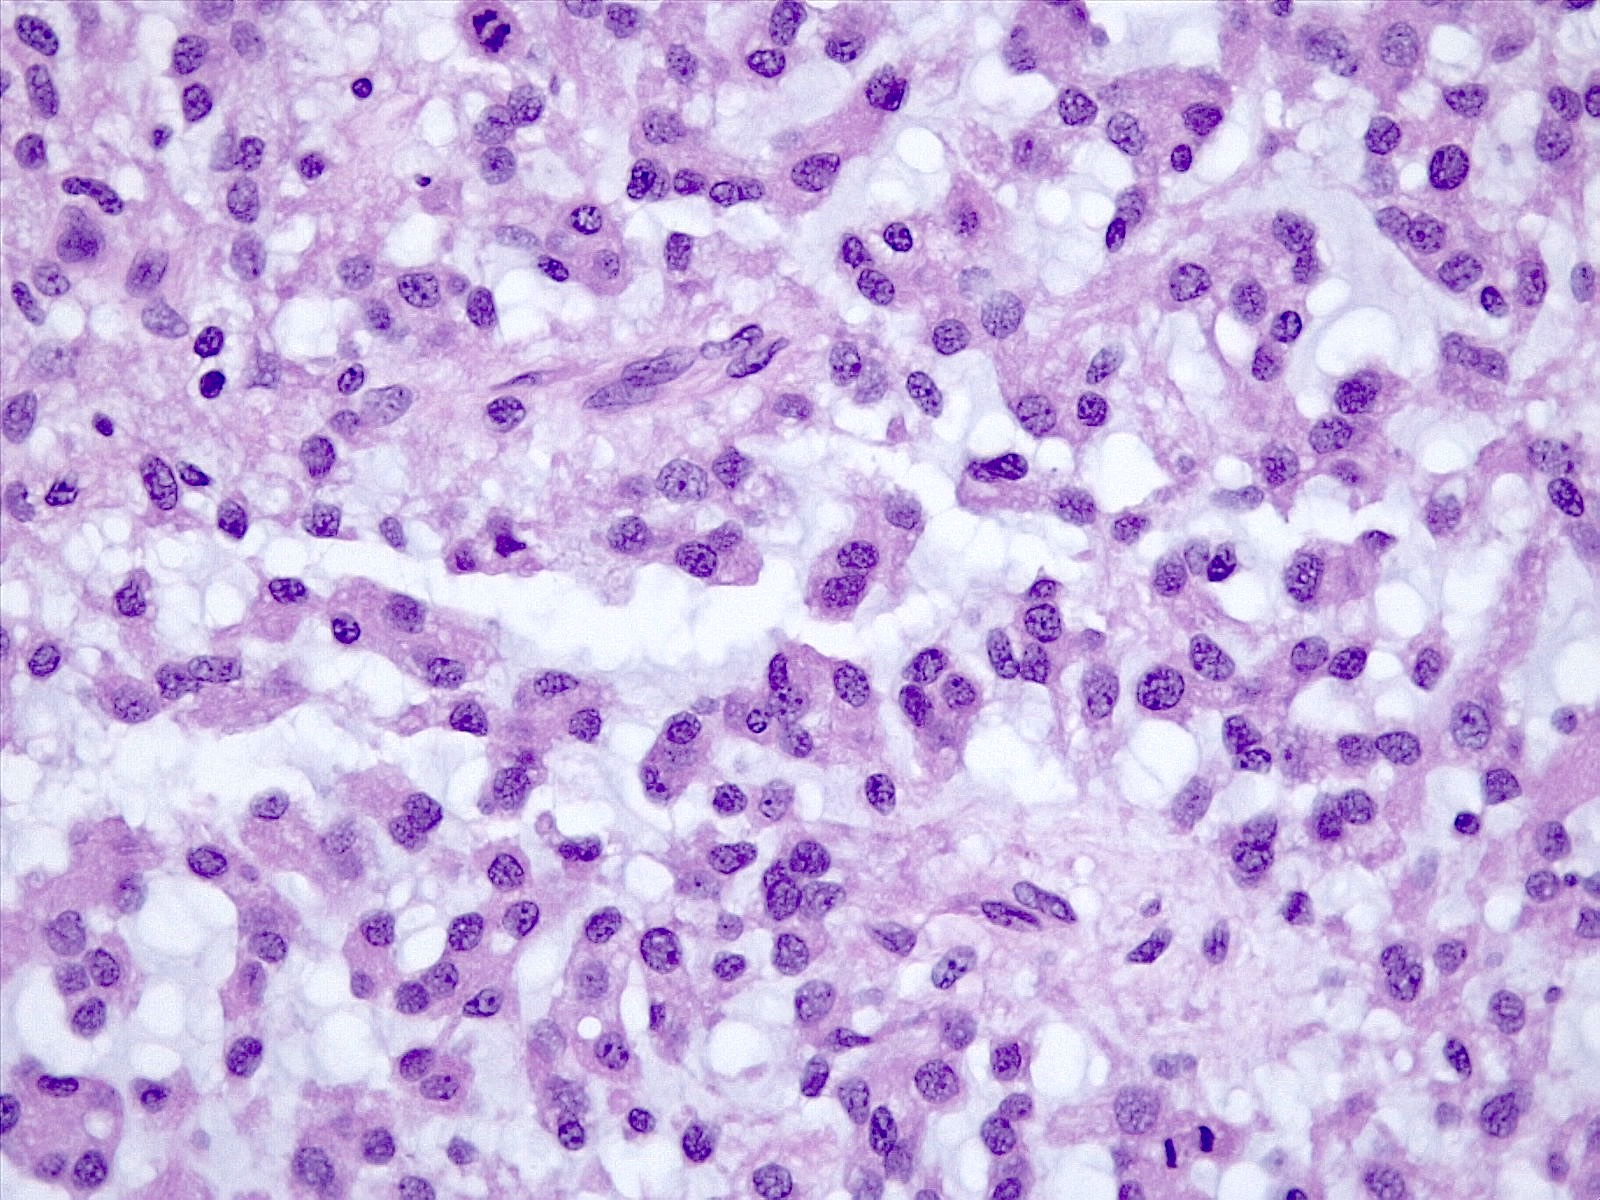

Microscopic (histologic) description

- Histologically reminiscent of chordoma, consisting of epithelioid cells or spindle cells (often partly vacuolated) that are arranged in cords within a pale basophilic myxoid matrix (Am J Surg Pathol 2000;24:899, J Neurooncol 2010;100:465, Histopathology 2013;62:1002)

- Chordoid morphology must be the predominant pattern for diagnosis of chordoid meningioma and CNS WHO grade 2 designation

- Interspersed areas of more typical meningioma are frequent but pure chordoid cases may be seen (Am J Surg Pathol 2000;24:899, J Neurooncol 2010;100:465, Histopathology 2013;62:1002)

- Atypical features may be seen, including mitoses, brain invasion, spontaneous necrosis, macronucleoli, increased cellularity, sheeting or small cells with a high N:C ratio (Am J Surg Pathol 2000;24:899, Acta Neuropathol Commun 2022;10:56, Histopathology 2013;62:1002)

- Lymphoplasmacytic infiltrate in 59.5% (Am J Surg Pathol 2000;24:899)

Microscopic (histologic) images